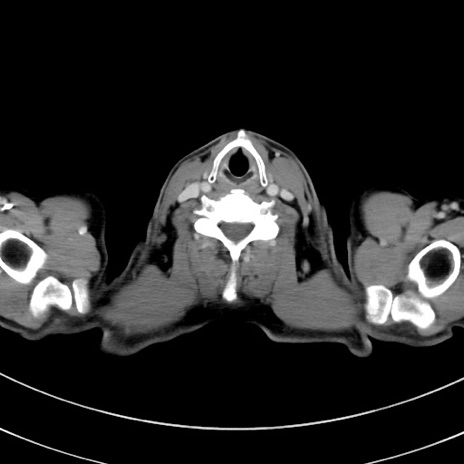

症例8(横断像)

【症例】 60歳代男性

【主訴】 黒色吐物

【現病歴】 4日前から嘔気自覚、2日前の朝食後にも嘔気あり、自分で手で嘔吐反射起こし嘔吐したところ血が混ざっていたため受診。

【既往歴】 5年前汎発性腹膜炎を伴う急性虫垂炎で手術、高血圧、前立腺肥大症、高脂血症

【身体所見】 腹部正中に手術癩痕あり 腹部平坦・軟圧痛なし膨満感あり

【データ】WBC 8400、CRP 4.54